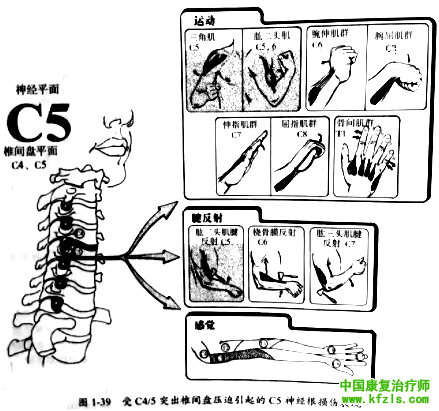

突出的椎间盘从上方压迫自椎间盘上方发出并行经椎旁椎间孔的神经根,并导致相应神经节段受累。如 C5和C6椎间盘突出将从上方压迫C6神经根(图1-33 )。

采用下述神经功能检査方法即可确定椎间盘突出的相应平面(图1-39至1-43)。